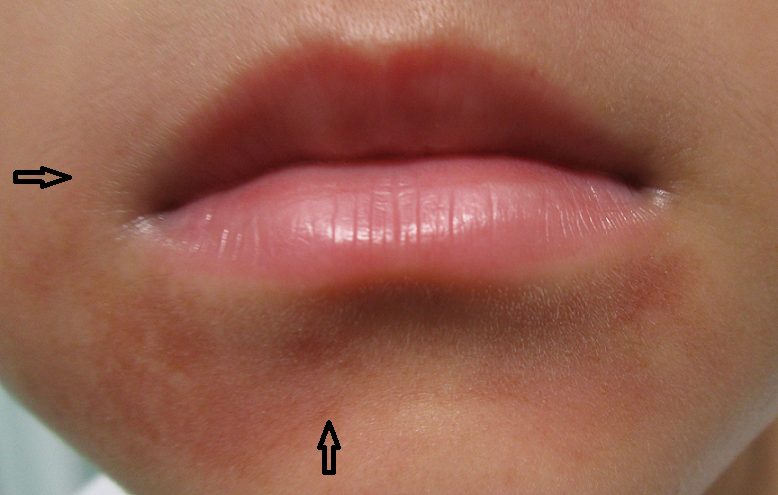

写真あり下唇の内側の一部が白くなり若干腫れている歯チャンネル歯科相談室。

写真あり下唇に口内炎のような白い出来物ができている歯チャンネル歯科相談室。

写真あり唇の裏に白いものが出来ています歯チャンネル歯科相談室。

唇のできもの 白いブツブツやザラザラの原因は? 症状別に解説 医師監修- SillHa.com - 歯と口と身体の健康メディア -シルハドットコム- SillHa.com - 歯と口と身体の健康メディア -シルハドットコム。

唇のぶつぶつの3つの原因「自然治癒する?」「お薬は?」水疱・白いできものなどMedicalook メディカルック。

唇に白い斑点ができる原因は?受診目安や日常生活での注意点も解説! – ココシカ。